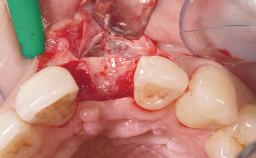

Immediate Flapless Placement of an Implant in a Maxillary Left Central Incisor Site

A 42-year-old female patient was referred to our clinic at the School of Dentistry of the University of São Paulo in November 2004, presenting a deficient restoration in the upper left central incisor. The clinical examination revealed no gingival retraction or any signs of gingival inflammation and, therefore, previous periodontal treatment was not considered. The patient presented a high lip line at full smile and a thin tissue biotype. This combination characterized a high-risk situation from an anatomic point of view, which required careful preoperative planning and cautious surgical execution.

Placement Protocol Immediate implant placement

Tooth Site Maxillary incisor or canine

Socket Morphology Single-root socket

Socket Integrity Sufficient, with intact bone walls